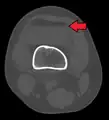

Lipohemarthrosis (presence of fat and blood from bone marrow in the joint space after an intraarticular fracture) seen on X-ray in a person with a subtle tibial plateau fracture

Lipohemarthrosis due to a tibial plateau fracture

Lipohemarthrosis due to a tibial plateau fracture- A tibial plateau fracture seen on X-ray